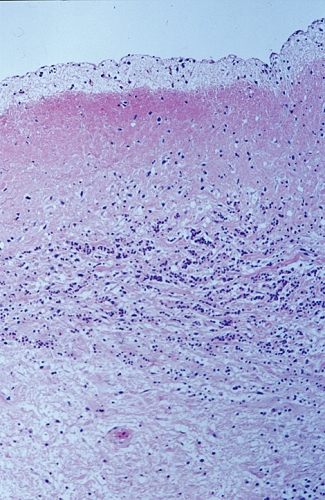

Figur 1 och 2 är PAD-bilder från mitralklaff från 2 av 14 kliniskt friska, 6 månader gamla grisar, som slaktades på vanligt sätt vid svenskt slakteri. Mitral- och trikuspidalklaffarna togs ut, och en del klipptes sterilt ner i transportmedium till bakteriologisk odling. Återstående del formalinfixerades, bäddades och färgades för mikroskopisk undersökning [2]. Inuti klaffarna fanns en anhopning av leukocyter (Figur 1), där streptokocker kunde framodlas hos 4 av 6 grisar.

Av avgörande intresse var att endotelbeklädnaden av såväl ovan- som undersida av klaffen var intakt och saknade ojämnheter, vegetationer eller andra förändringar på sin yta (Figur 1). Däremot fanns nekrotiskt material och granulationsvävnad inuti vissa av klaffarna, i vilka infektionen/inflammationen hunnit utvecklas längre. I detta mer framskridna infektionsskede hade även endokardiet på klaffytan börjat påverkas (Figur 2).